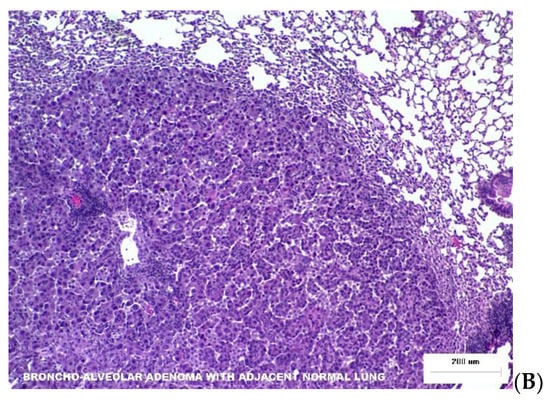

Two photomicrographs are included in Figure 2 illustrating the types of dose-dependent lung pathology observed 16-months after exposure to Silicon ions.

Figure 2. Representative photomicrographs of lung tumor histopathology at necropsy 16 months post irradiation. (A) The yellow arrow points to Broncho-Alveolar Adenoma with adjacent normal tissue from an animal that was irradiated with 0.04 Gy Silicon. (B) Histiocytic Sarcoma in lung tissues from animal exposed to 0.16 Gy Silicon ions.